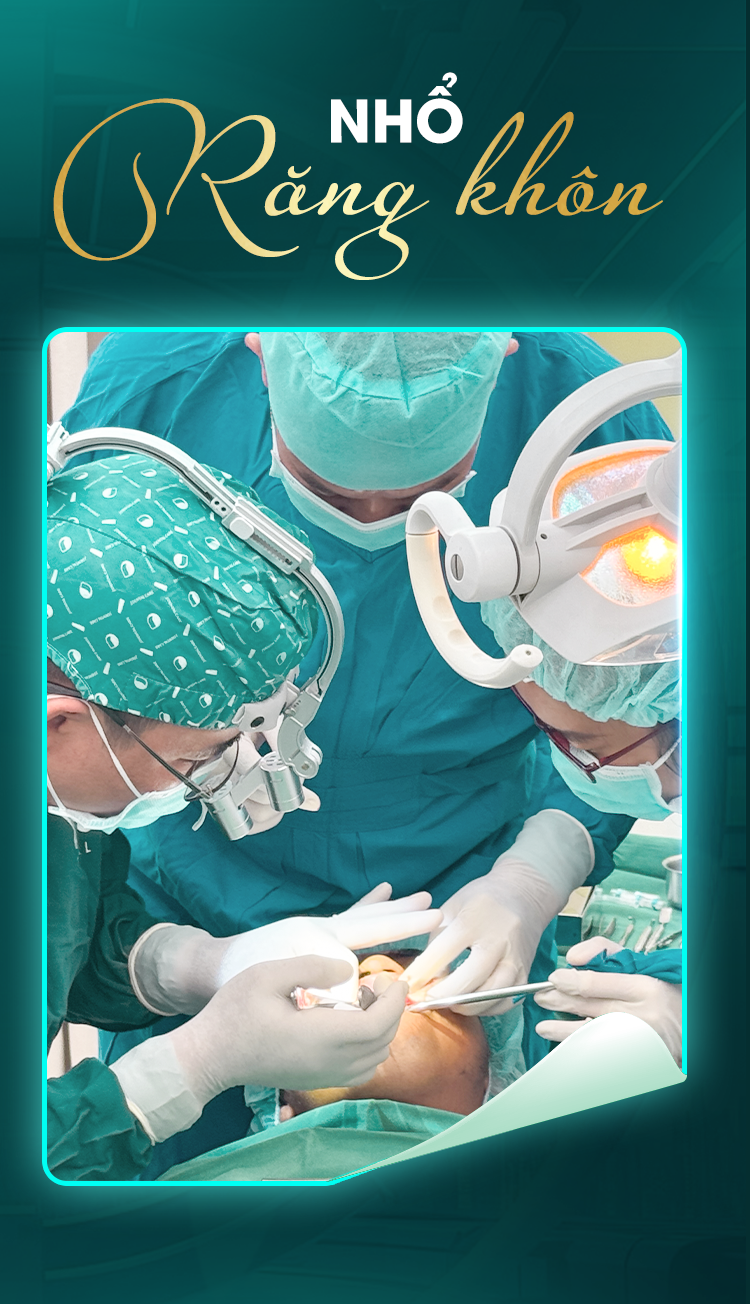

Nhổ răng khôn an toàn - Tạm biệt phiền toái

Tiểu phẫu răng khôn là quy trình loại bỏ những chiếc răng số 8 (răng khôn) mọc lệch, ngầm gây đau nhức, viêm nhiễm hoặc ảnh hưởng đến các răng kế cận, giúp bạn giải tỏa khó chịu và bảo vệ sức khỏe răng miệng.

Tiểu phẫu răng khôn